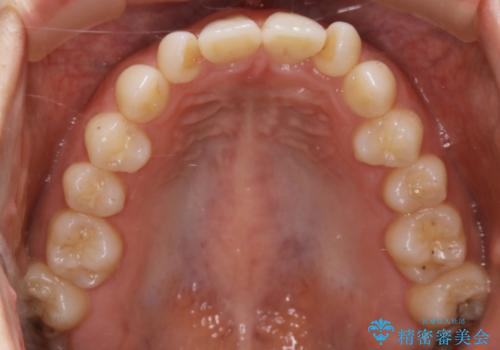

- 前から2番目の歯が捻じれていることが気になるとご相談にいらした方です。

インビザラインFULLで治療を行いました。

上の前から2番目の歯は、一般的に周囲の歯と比べて小さく、動きづらい歯であると言われています。前歯にゴムかけを行うことで理想的な位置まで歯を動かしてくることが出来ました。